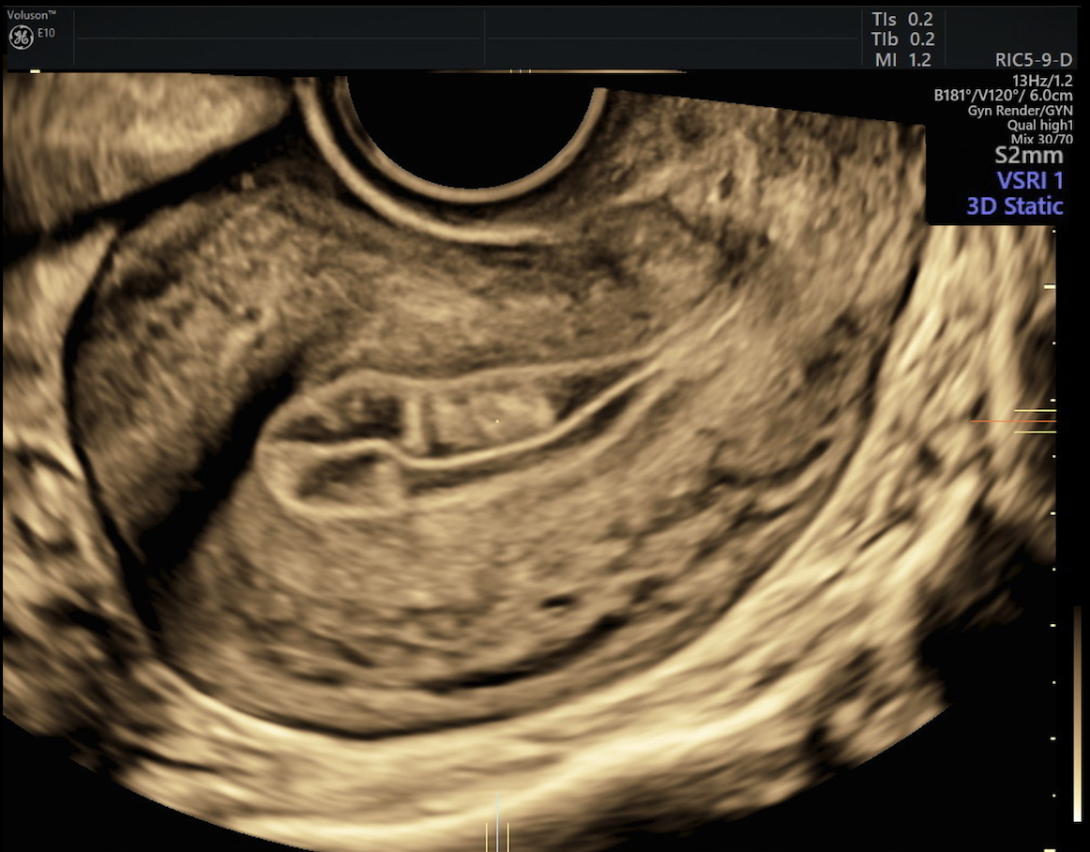

Imagem de ultrassom 3D mostrando nódulo de mioma uterino entre as setas